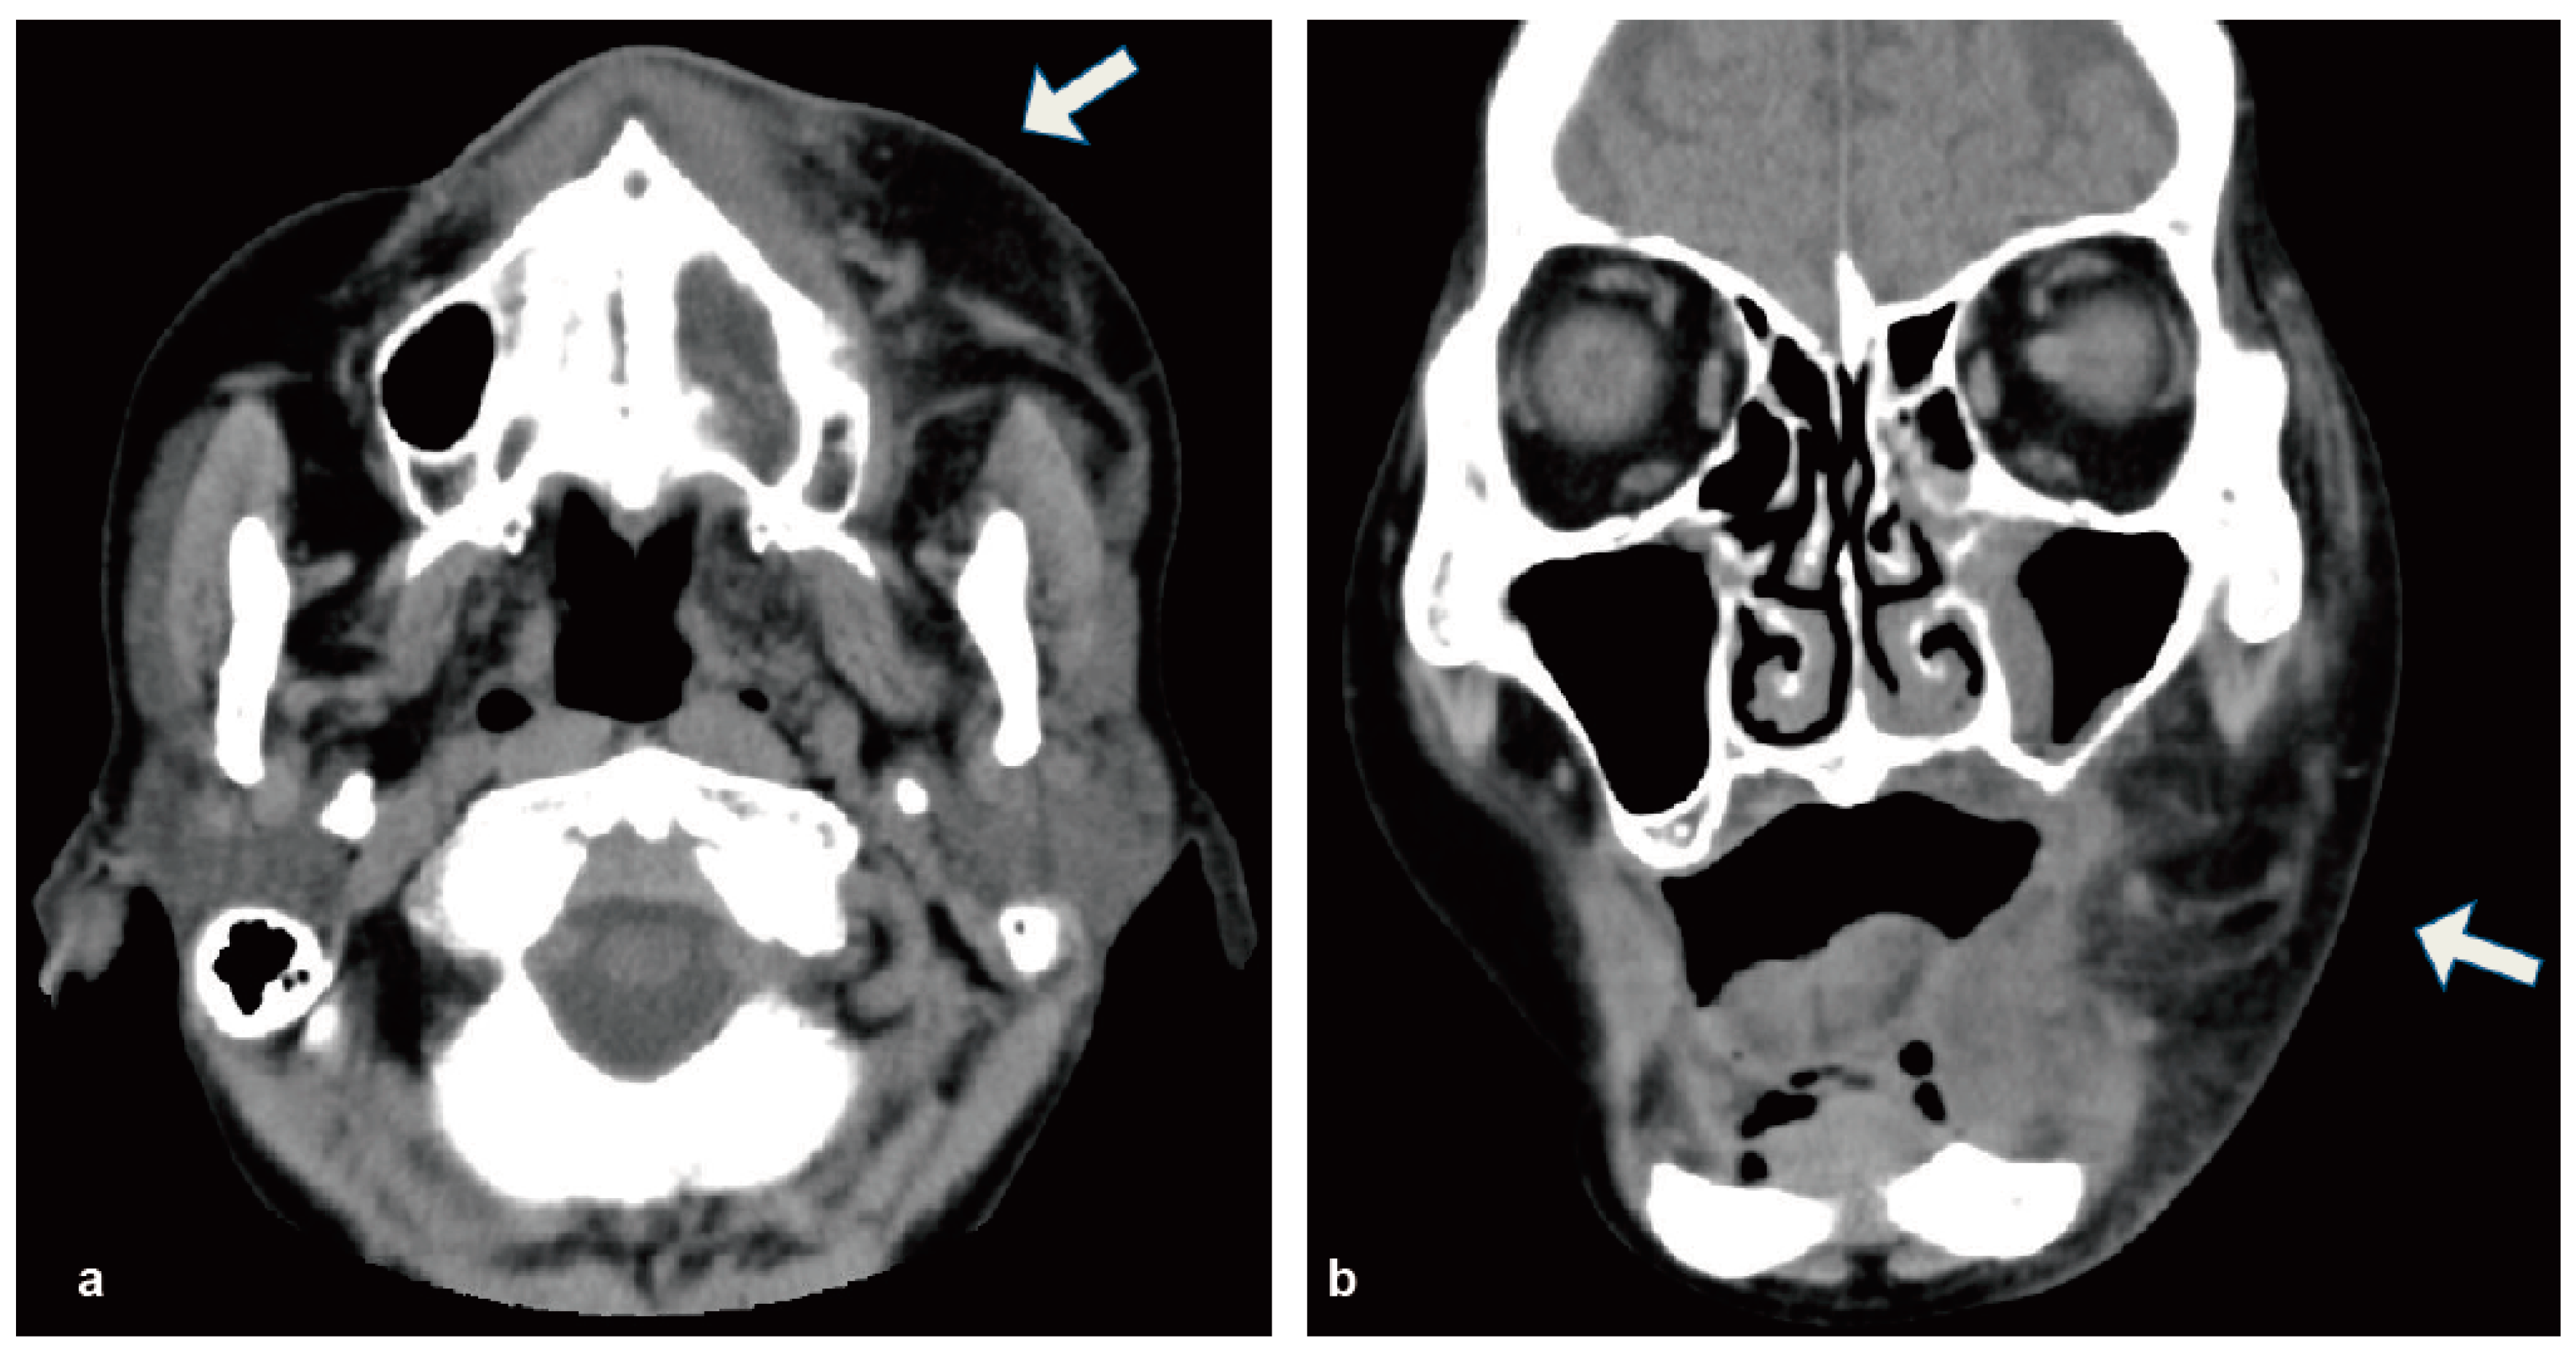

2. Case Report